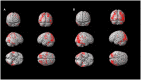

Results: Three progressive electro-clinical stages were identified. The early phase was characterized by rare, generalized tonic-clonic and focal visual seizures, followed by the occurrence of myoclonus after a period ranging from 2 to 12 months. The intermediate stage, usually occurring 2 years after the onset of epilepsy, is characterized by a worsening of epilepsy and myoclonus associated with progressive dementia and cerebellar signs. Finally, the late stage, evolving after a mean period of 7 ± 1.41 years from the onset of the disease, was characterized by gait ataxia resulting in bedriddenness, severe dementia, daily/pluri-daily myoclonus, drug-resistant epilepsy, clusters of seizures or status epilepticus, and medical complications. Amyloid (CSF Aβ42, amyloid PET) and neurodegenerative (CSF p-tau181 and t-tauAg, FDG-PET) biomarkers indicate a pattern of cognitive impairment of the non-Alzheimer's disease type. A total of 80% of the LD patients showed more severe hypometabolism in the second FDG-PET scan compared to the first scan performed in a lower phase; the lateral temporal lobe and the thalamus hypometabolism were associated with the presence of intermediate or late phase.

Conclusions: Three electroclinical and 18F-FDG PET evolutive stages are useful biomarkers for the progression of LD and could help to evaluate the efficacy of new disease-modifying treatments. The combination of traditional CSF biomarkers improves the diagnostic accuracy of cognitive decline in LD patients, indicating a cognitive impairment of the non-Alzheimer's disease type.